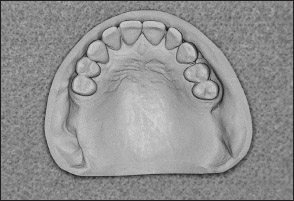

• Kennedy Class I arch: Characterized by bilateral edentulous areas located posterior to the remaining natural teeth (Figs 1-11 and 1-12).

Fig 1-11 Maxillary Kennedy Class I arch.